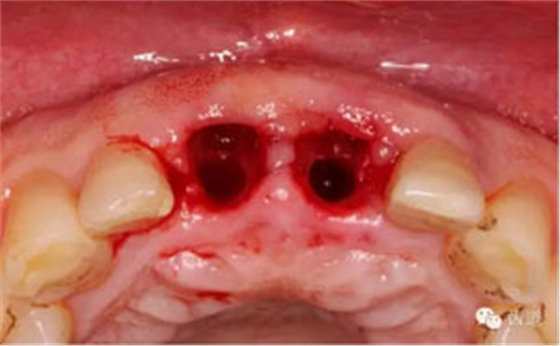

備洞完成

植入種植體(唇側(cè)留2-3mm jumping gap)

確定植入深度(齦下3-4mm)